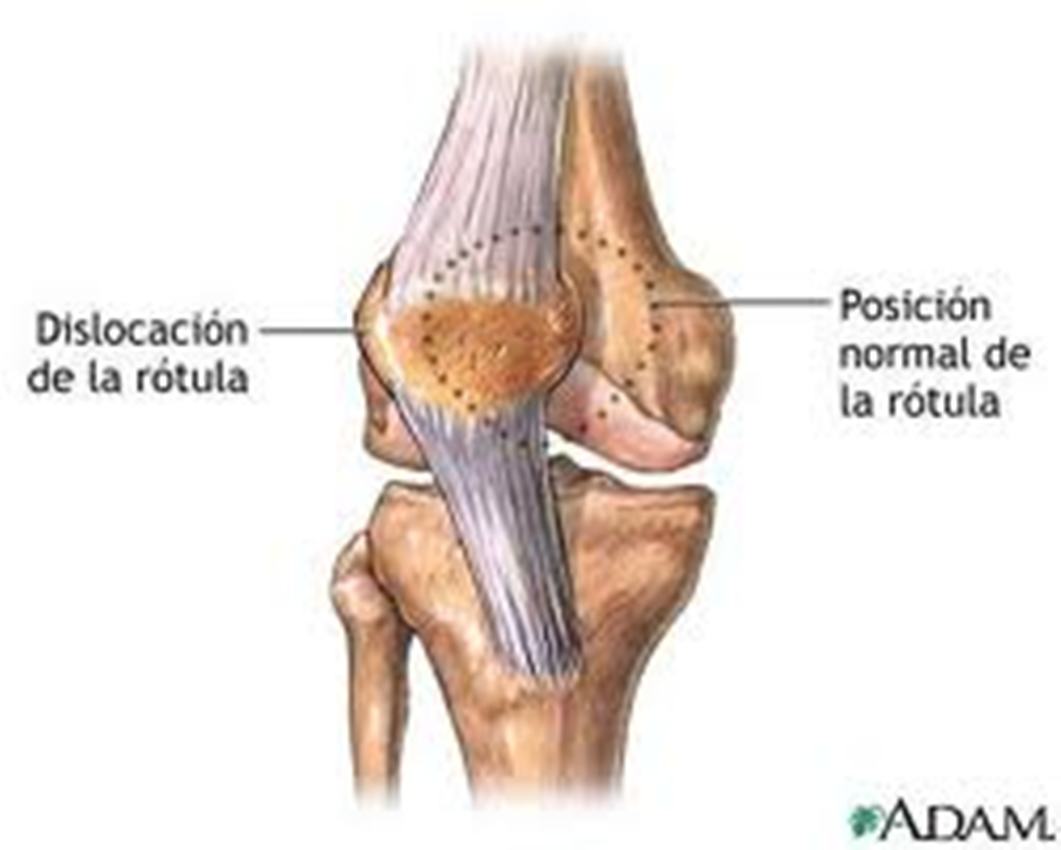

Сам по себе вывих надколенника возникает редко, но при врожденных аномалиях коленного сустава или как последствие других травматических повреждений колена вывихи надколенника занимают второе по частоте место среди повреждений коленного сустава. Что значит приставка «привычный»? Она говорит о периодическом повторении такой травмы.

Чтобы произошло смещение надколенника, который мы чаще называем коленной чашечкой, необходима колоссальная нагрузка на ногу. Поэтому чаще всего причиной этой травмы становятся чрезмерно активные занятия спортом и связанные с ними падения на колени, боковые удары в колено (медиальный и латеральный подвывих надколенника), резкие разгибания коленного сустава

При острой травме надколенника развиваются характерные симптомы. Пациент ощущает резкую сильную боль, коленная чашечка визуально смещается, развивается отек сустава. Обычно ногой очень боль и сложно двигать – согнуть или разогнуть, поэтому нужно немедленно обратиться к врачу.

Под вывихом надколенника подразумевают такое патологическое состояние коленной чашечки, при котором происходит ее смещение, сопровождающееся неприятными и болезненными ощущениями.

Вывих надколенника можно определить по совокупности совершенно типичных симптомов:

- Надколенник изменяет свое положение, а так же смещается относительно своего положения.